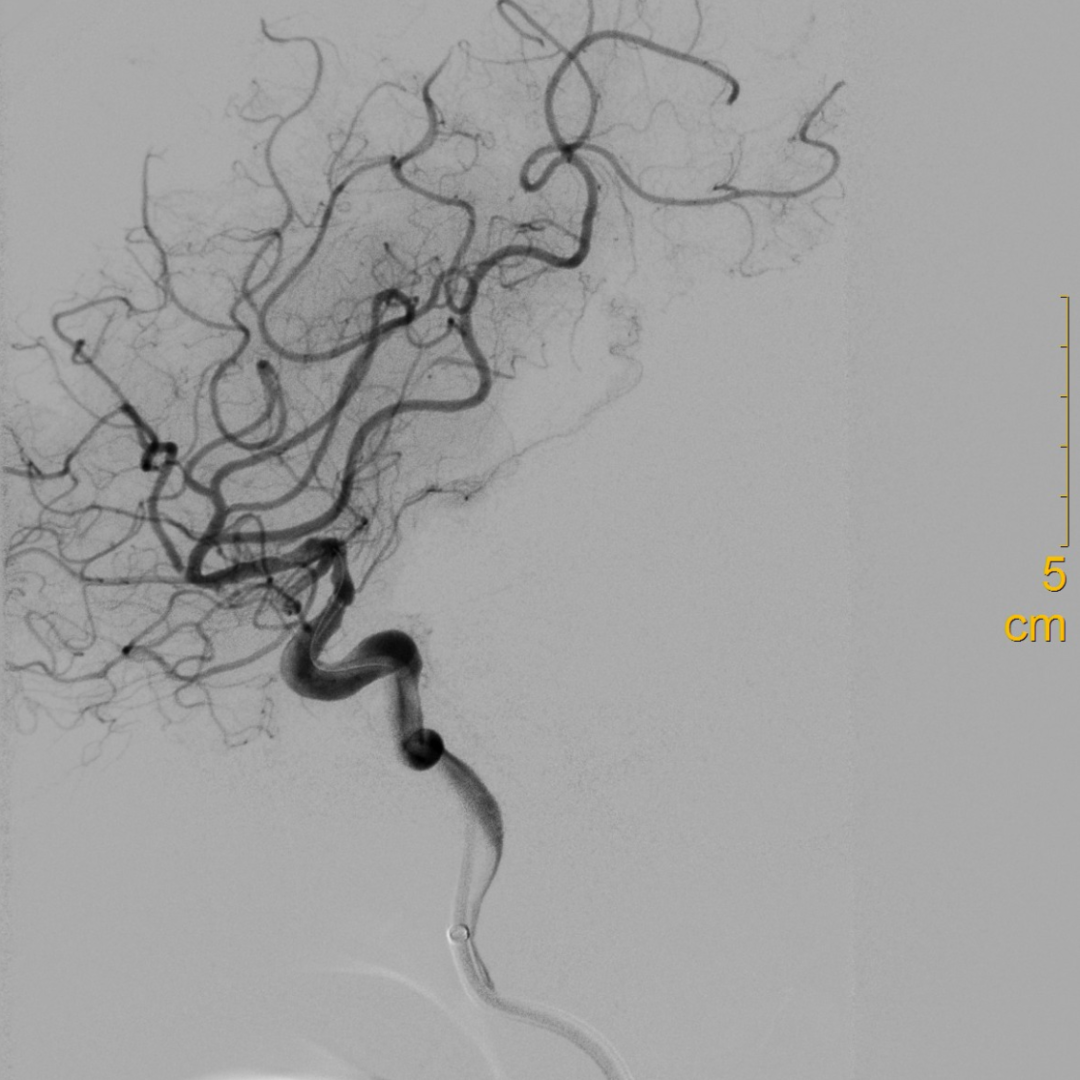

造影可见闭塞残端细小,结合多时相CT,考虑倾向于狭窄性病变。

什么叫桡鞘【例久弥新】寻道于桡——瑞康通5.5F IntroSky X导管鞘经桡动脉行右侧大脑中动脉取栓一例_https://www.jmylbn.com_新闻资讯_第14张